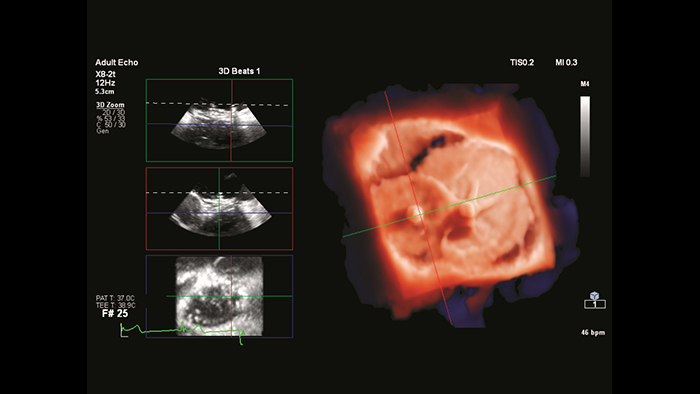

Modelowanie 3D z użyciem systemu IntelliSpace Portal

Segmentacja modelu serca w systemie EchoNavigator